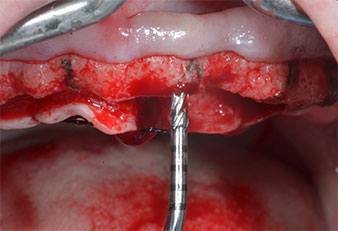

Пиезоелектрически инструмент с диамантено покритие с форма на пламък (Piezomed I1) e използван за маркиране на позициите на имплантите и за пилотна подготовка (Фиг. 3). Препарацията беше извършена с внимателни вертикални движения, с намалена мощност, пълна иригация и лек натиск (под 300 g) След това се приложи пилотен инструмент (Piezomed I2A/ I2P) за първоначално увеличение на диаметъра на имплантното ложе с 2 mm (Фиг. 4), последвано от 3 mm разширение (Фиг. 5)

В случай на твърда кост, цялата поредица от инструменти, включително междинните инструменти Piezomed Z25P и Z35P, трябва да се използват за разширяване на остеотомиите.

Те също така са предназначени за подготовка в близост до синусовата мембрана във връзка с вътрешни аугметационни процедури или когато има по-малко от 4 mm остатъчна височина на костта.

В настоящия случай инструменти Z25P и Z35P не са използвани поради сравнително меката задна кост, която лесно се обработва с I3A/I3P.

Поради сравнително твърдата кост (D2) в тази област, 10-милиметровото имплантно ложе в позиции 11 и 21 беше завършено с ротационен дрил с диаметър 4 mm в комбинация с W&H хирургичен обратен наконечник WS-75 L, W&H имплантологичен мотор Implantmed и опционалния W&H Osstell ISQ модул. За разлика от това, благодарение на меката кост, дисталните зони се подготвят до окончателен диаметър 3 mm, използвайки накрайник за Piezomed I3P. Имплантите най-накрая са поставени трансгингивално, за да остеоинтегрират за три месеца (Фиг. 6-10). Съществуващата протеза се фиксира на четирите временни импланта (Фиг. 8).